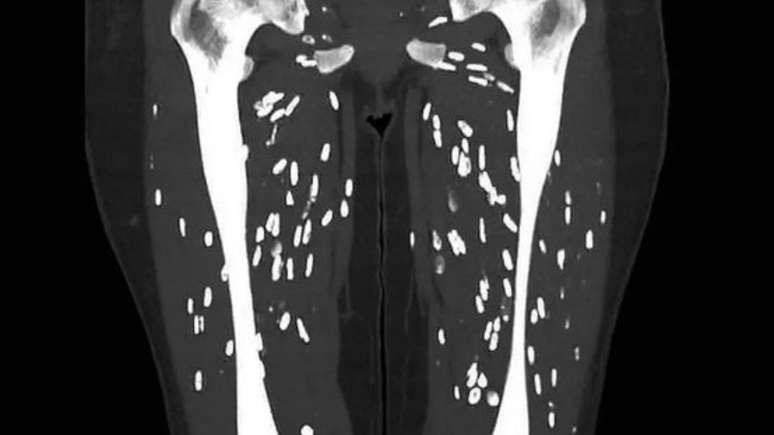

Com mais de seis milhões de visualizações, o médico da Universidade da Flórida, Sam Ghali, levantou um alerta importante nas redes sociais. Utilizando a plataforma X, ele destacou o risco de exposição à cisticercose por meio do consumo de carne de porco mal cozida. Essa condição é causada pelo contato com fezes humanas infectadas pelos ovos da tênia.

O processo de infecção ocorre quando os humanos ingerem esses ovos através de alimentos contaminados, água ou superfícies sujas. Ghali explicou como os cistos da Taenia solium se desenvolvem no corpo humano, podendo levar a sérias complicações se não tratados adequadamente.

Quando os ovos são ingeridos novamente, seja por humanos ou porcos, as larvas penetram na parede intestinal e entram na corrente sanguínea. Elas podem migrar para diversos órgãos do corpo, como cérebro, olhos, tecidos subcutâneos e músculos, onde formam cistos chamados cisticercos.

Exames de imagem, como tomografia computadorizada ou ressonância magnética, são frequentemente utilizados para identificar cisticercos em órgãos como o cérebro ou os olhos. Além disso, testes de laboratório podem detectar anticorpos contra a Taenia solium no sangue.